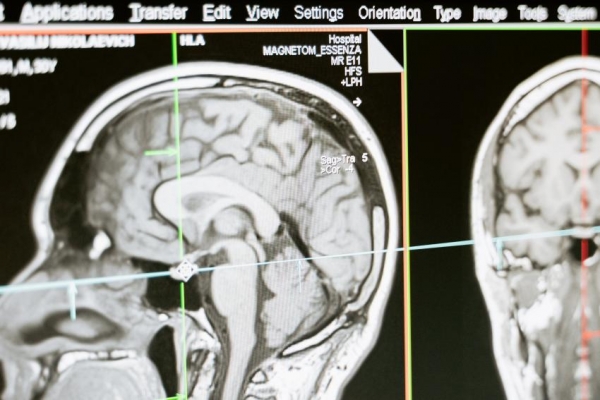

Названы неочевидные симптомы развития аденомы гипофиза. На изменения в организме указал нейрохирург ЕМС Глеб Сергеев.

Гипофиз руководит эндокринной системой, поэтому развитие в нем опухолей может сказаться на всем организме. Внутренние процессы могут приводить к тому, что в области гипофиза начинает расти аденома. Чаще всего на нее указывает выпадение волос, проблемы со зрением и бесплодие. Глеб Сергеев отмечает, что на некоторые из признаков наличия проблемы пациенты не обращают внимания. Некоторые из них не жалуются на остроту зрения, но им труднее распознавать оттенки зеленого, красного и белого. Иногда при аденоме гипофиза ухудшается терморегуляция, появляются проблемы не только с волосами, но и с ногтями. Врач указал также на изменения характера и эмоциональности, сильные перепады давления и веса. При данном недуге фиксировались увеличения размеров носа, ушей, пальцев, языка и надбровных дуг.